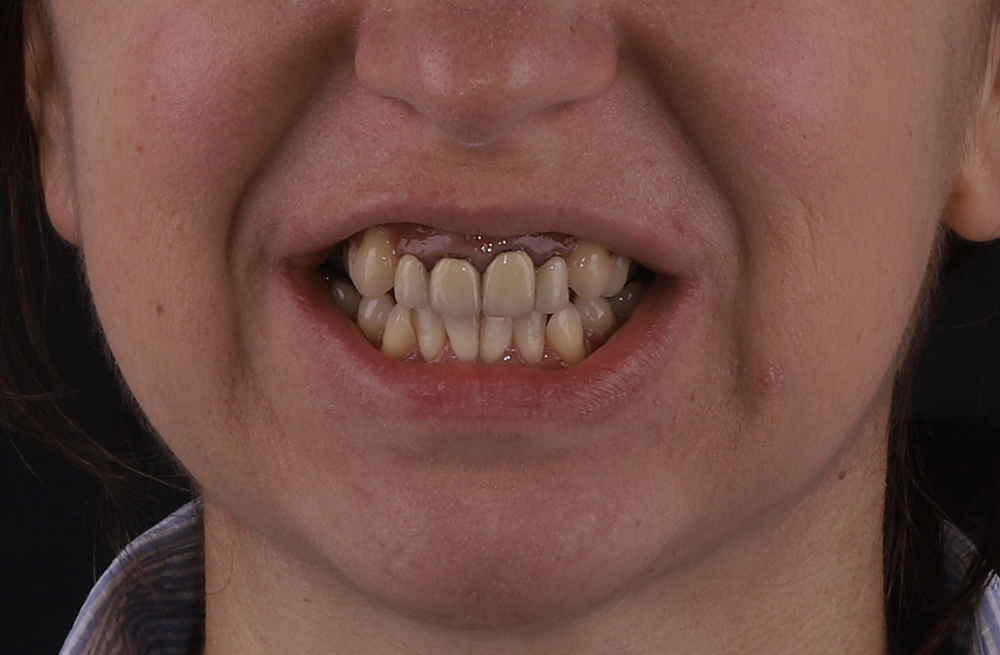

Ортодонтическое лечение с генерализованным пародонтитом